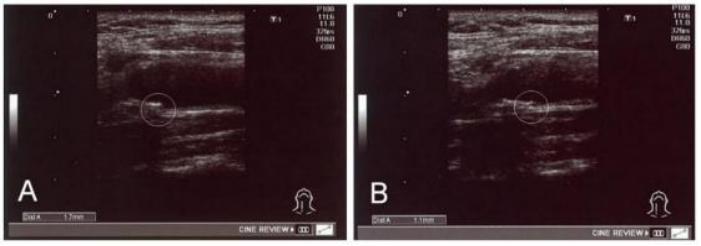

干细胞有效缓解动脉粥样硬化, 还血管“畅通无阻” 根据2021年《中国心血管健康与疾病报告》 ,中国目前有2.45亿高血压 ,4亿高血脂 ,6.7亿高血糖和2亿高 尿酸患者。放眼全球 ,每年有70%的死亡都和这四高相关。“ 四高” ,就是我们长寿路上最大的绊脚石。 北京大学的一项研究显示:30-79岁中国人中,约2亿人有颈动脉粥样硬化,1.5亿人有颈动脉斑块。在世界范围内,动脉粥样硬化血栓形成导致的死亡人数占全部死亡人数的52%,远远超过了第二位死因的肿瘤(24%)。 动脉粥样硬化,很多人看到这个词就一头雾水:粥要硬化?其实,它是一种非常常见的疾病,相信这样的报道我们并不陌生: 动脉粥样硬化是动脉硬化性血管病中最常见、最重要的一种疾病,也是冠心病、脑卒中、外周动脉疾病(PAD)和肾病主要病理的诱因,在中老年群体中尤为普遍。 什么是动脉粥样硬化 动脉粥样硬化是一种典型的慢性炎症性血管病变,为心血管病的主要病理学基础。动脉粥样硬化(atherosclerosis,AS)主要影响动脉内膜,是由于脂质成分和炎性物质沉积在动脉血管内壁,形成外观像小米粥样的斑块,导致动脉变窄变硬、弹性降低、阻碍血流,继而造成器官缺血损伤,它是脂质代谢紊乱导致的、以血管炎症反应和免疫反应失衡为主要病理基础的、与衰老相关的慢性退行性疾病。目前研究发现, 血管内皮细胞、平滑肌细胞和免疫细胞均参与了动脉粥样斑块形成、进展和破裂等各个阶段。 AS的发展是一个缓慢持续进行的过程,初期动脉粥样硬化常无任何临床症状,通常不会引起人们的注意,但当血管壁上沉积着的“小斑块”逐渐增多、增大、堵塞血管,使血流变慢,严重时使血流被中断,会诱发严重疾病,包括冠心病(心绞痛、心肌梗死)、脑卒中以及外周血管疾病等。 动脉粥样硬化病因复杂,基于细胞层面的微观分析,动脉内皮细胞功能发生障碍是动脉粥样硬化病变的第一步,血管壁内皮损伤如果不能及时修复,就会引发炎症以及粥样斑块的产生,而炎症反应在动脉粥样硬化的发生及其并发症形成过程中起着重要作用。 动脉粥样硬化的症状有哪些? 动脉粥样硬化可发生于不同的部位,引发的症状也是有所区别的。 1、冠状动脉粥样硬化 病变较轻时患者没有明显症状;严重时可引起心绞痛、心肌梗死等疾病,患者会出现胸痛、胸闷、大汗等症状,也可能出现恶心、呕吐、腹痛等症状。 2、颈动脉或脑动脉粥样硬化 病变较轻时患者也没有明显症状;病情较重时可引起脑卒中,患者会出现头痛、头晕、短暂性意识丧失、恶心、呕吐、视物模糊、偏瘫、言语不清、走路不稳等症状。 3、下肢动脉粥样硬化 病变较轻时患者没有症状;严重时可引起下肢动脉狭窄或闭塞,患者可以出现下肢麻木、疼痛、间歇性跛行(间歇性跛行,是指走路时产生疼痛等症状并逐渐加重,休息后缓解,再走路再产生、再加重)。 动脉粥样硬化的常规治疗 除去年龄和家族病史外,具有胆固醇水平异常、甘油三酯偏高、高血压、吸烟、胰岛素抵抗、糖尿病、超重或肥胖等高危因素人群更容易患动脉粥样硬化。 目前对于动脉粥样硬化的治疗主要分为药物治疗和手术治疗,但是临床使用的抗AS药物存在肝肾损伤、横纹肌溶解等副作用,而外科手术(俗称“搭桥”)或介入(俗称“放支架”)治疗等手术疗法创伤较大,住院时间长,恢复正常生活慢,因此,如何攻克它成为临床医学的研究重点。 动脉粥样硬化是一种由内皮功能障碍、脂质积累和免疫细胞募集驱动的慢性炎症状态,导致动脉壁内膜层内形成斑块。因此,治疗旨在稳定斑块、抑制炎症和降低高脂血症。 生物医学领域的专家一直在探索新的防治策略,而干细胞的出现为这一难题带来了全新的解决方案。 干细胞干预动脉粥样硬化,还血管“畅通无阻” 干细胞是一种未充分分化,尚不成熟的细胞,具有再生各种组织器官的潜在功能。研究发现,干细胞在人体内可向损伤部位趋化迁移及发挥免疫调节功能,大量科学研究表明,它在减缓血管斑块的形成,尤其在调节脂质代谢、免疫抗炎和保护内皮细胞等方面作用显著。 最近的研究表明,在动物模型中,间充质干细胞能够通过降低血脂异常、炎症和抑制内皮细胞功能障碍和斑块形成,提供免疫抑制、再生和动脉粥样硬化保护作用。 发表在《Regen Med》杂志上的综述对间充质干细胞在动脉粥样硬化治疗中的潜在机制进行了详尽介绍。 另一项发布在世界顶级科学杂志《自然》上的一项报告证实了间充质干细胞可有效改善动脉粥样硬化。MSCs显著影响病变发展,主动脉根部病变发展减少33%(由于极低密度脂蛋白水平的降低,血清胆固醇降低了33%)。这些病变中巨噬细胞减少56%,T细胞数量减少61%。我们在这里首次表明MSC治疗不仅影响炎症反应,而且显著降低小鼠的血脂异常。这使得间充质干细胞成为动脉粥样硬化治疗的有力候选者。 日本东京的研究院开展了一项间充质干细胞改善高血脂的临床试验。研究人员采用干细胞静脉注射的方法对动脉硬化的患者进行治疗,在治疗过程中,无发现不良反应。 治疗结果发现脂肪干细胞移植可显著改善患者血清中的高密度脂蛋白胆固醇、低密度脂蛋白胆固醇和残余颗粒(RLP)胆固醇水平。 其中,一位高血脂患者在接受干细胞治疗后,颈总动脉中层厚度( IMT )值从1.7mm下降到1. 1mm。也就是说,这位患者从“颈动脉狭窄”改善为“ 内膜增厚”,发生心脑血管疾病的风险大大降低。 截止2022年08月15日,在美国国立卫生研究院的最大临床试验注册库http://clinicaltrials.gov上注册的干细胞治疗动脉粥样硬化的临床研究就达54项。 越来越多的研究表明干细胞具有修复损伤组织的潜能,干细胞技术的发展为损伤血管修复提供了新方向。 间充质干细胞干预动脉粥样硬化的机制 调节脂质代谢紊乱 通过调节多种酶的合成发挥调脂效果 通过改变参与脂肪酸生物合成和氧化的转录因子的表达来调节脂蛋白的合成过程。 减少内皮功能障碍 增强内皮细胞分化,提高内皮细胞活力,加速受损动脉内膜的修复过程,减少或消除斑块的堆积。 减少炎症细胞 抑制CD4和CD8T细胞并增加Treg的比例。 抑制树突状细胞分化和成熟,从而减少T细胞活化。 促进巨噬细胞的表型从促炎状态转变为抗炎状态,从而产生抗炎细胞因子谱,减少泡沫细胞的形成 增加斑块稳定性 减小动脉粥样硬化斑块的体积,从而赋予了更大的斑块稳定性。 增加纤维帽厚度,增加平滑肌细胞和胶原蛋白含量,形成更稳定的斑块。 减弱了动脉粥样硬化斑块的炎症环境,这减少了斑块浸润并增强了稳定性。 综上所述,干细胞可以减轻内皮功能障碍、降低血清脂质水平、抗炎并稳定现有的动脉粥样硬化斑块,干细胞移植可缓解动脉粥样硬化的发展,大大降低了心脑血管疾病的发生风险。随着对干细胞临床治疗的进一步研究,相信未来将造福更多动脉粥样硬化患者。